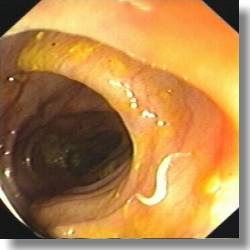

Enterobius vermicularis (oxiurii)